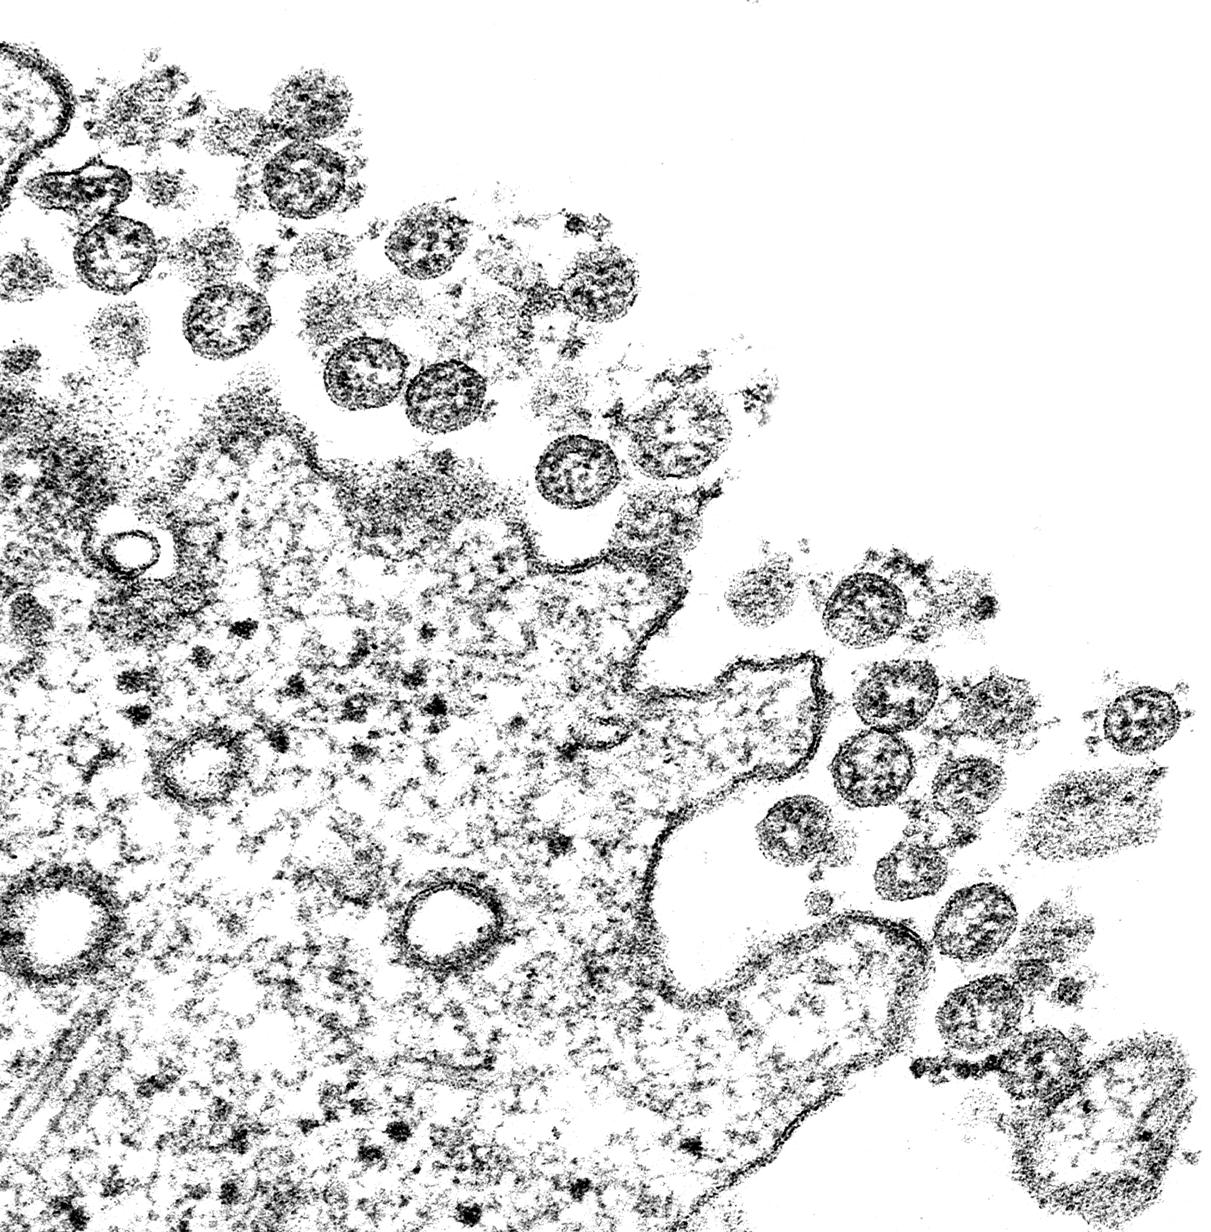

LET’S WORK TOGETHER

UAH and collaborators make bioscience news

page 4